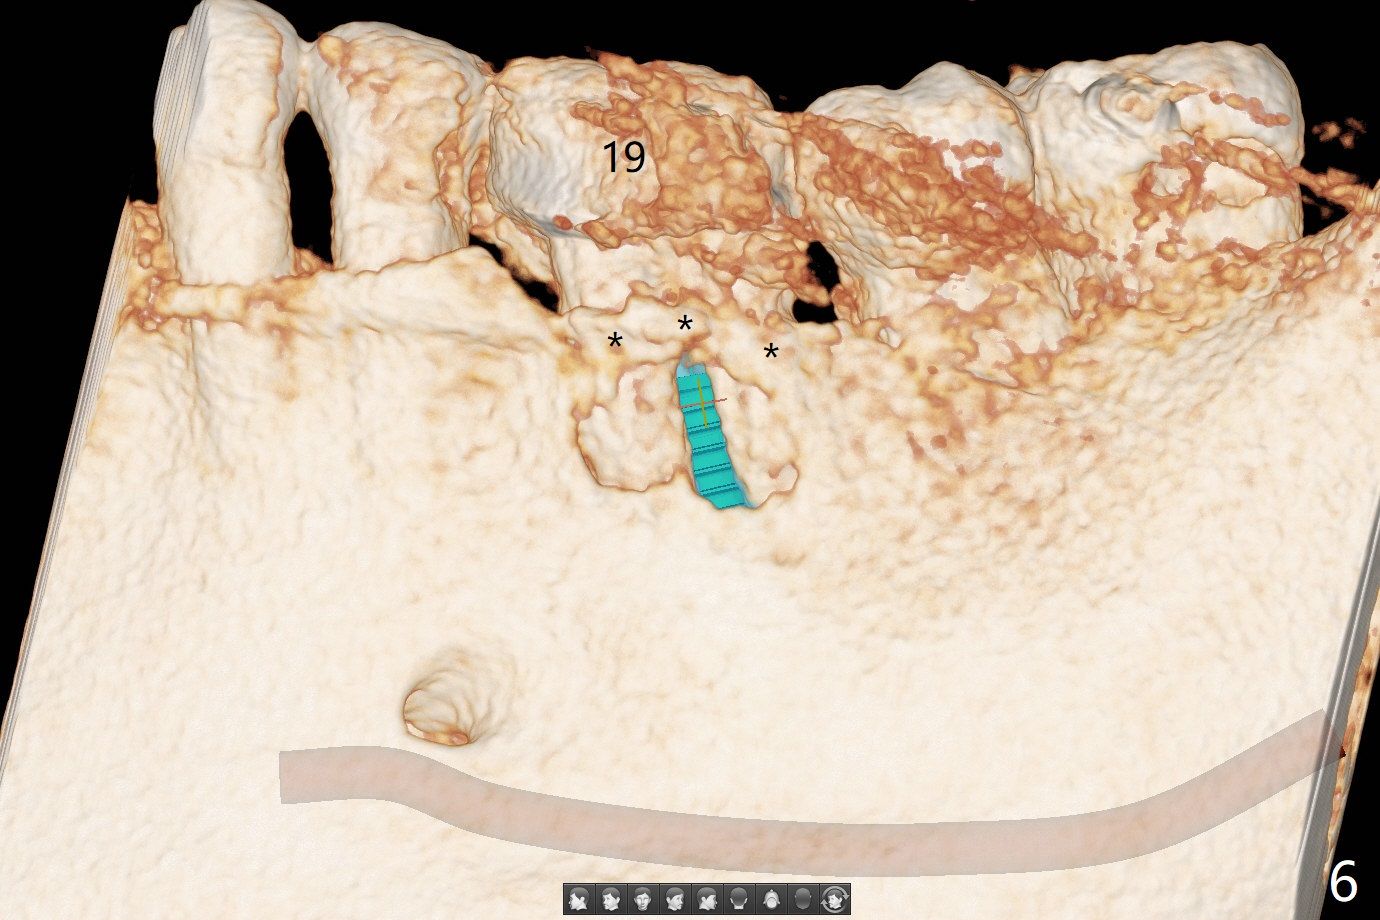

The tooth #19 of a 61-year-old man develops pain 9 years post complicated RCT (Fig.1). Periradicular radiolucency is more around the mesial root (Fig.2) than the distal one (Fig.3). Section the crown to check whether the distal margin is restorable. Remove the mesial root to determine whether the distal one is salvageable or not. If not, place a 5x15 mm bone-level implant with guide. To reduce the chance of screw loosening, consider placing a tissue-level implant (Fig.4,5). Preserve the buccal crestal bone (Fig.6 *) during extraction and debridement, which keeps the socket open for bone graft and healing. Draw blood for PRF PRN for membrane and sticky bone.